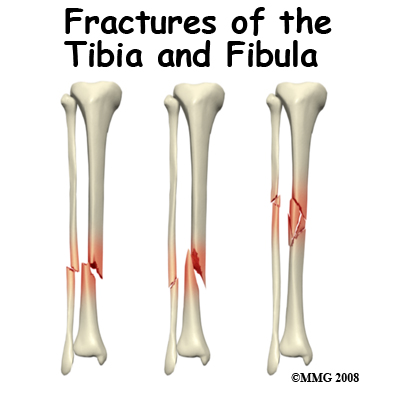

Adult Lower Leg Fractures

In this guide we are concerned with fractures of the lower leg between the knee and ankle. The two bones in the lower leg are the tibia and fibula. We will limit this discussion to fractures of the shaft, or mid section of these two bones. Fractures of the lower end of the tibia and fibula are covered in ankle fractures. Fractures of the upper end of the tibia are covered in knee fractures.The tibia bone is the largest and most important bone of the lower leg. It is quite vulnerable to injury. T...